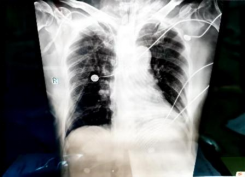

急诊胸部正位片: 1.双肺透过度减低,纹理模糊,散在索条,请结合CT 2.心影饱满,结合临床相关检查3.双侧胸腔积液4.双侧多发肋骨走行欠规整

2025/11/20复查床旁胸片:1.双肺纹理增强,模糊,双肺散在条片影,请结合临床及CT检查2.右肺门影增大,结合CT 3.心影饱满4.双侧胸腔积液,左侧为著5.双侧多发肋骨走行欠规整,结合病史 6. 气管插管后

2025/11/23床旁胸片:1.肺水肿可能,较2025-11-20DR改善,请结合临床及实验室检查2.左侧胸腔积液3.双侧多发肋骨走行欠规整,结合病史

2025/11/27床旁胸片:1.双肺纹理增多,增粗,较2025-11-23DR相仿2.右肺门影增大,

较前相仿3.左侧胸腔积液

2025/12/01床旁胸片:1.左侧胸腔积液2.双肺感染,治疗后复查

2025/12/08床旁胸片提示双肺感染好转。血液净化支持下氧合指数逐渐改善,予以血液净化下机。

2025/11/16: 床旁胸片

2025/11/20床旁胸片

2025/11/23床旁胸片

2025/12/01床旁胸片

2025/12/08床旁胸片